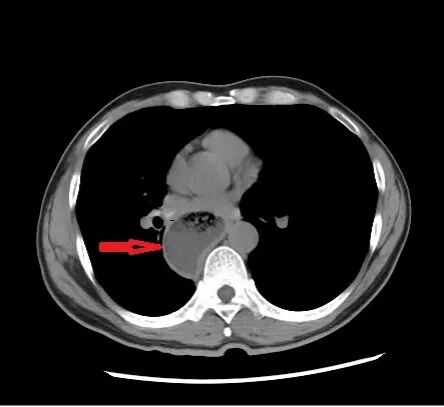

患者收治入院后,医生先后为其完成胃镜、上消化道造影、腹部CT等专科检查。胃镜检查提示,食管下端呈典型“鸟嘴样”改变,胃镜通过困难,食管上段明显扩张;上消化道造影提示,食管下端狭窄呈鸟嘴状,食管整体扩张、蠕动减弱,钡剂通过贲门受阻;腹部CT提示,食管扩张明显,管腔内可见积液积气。

结合症状与影像学检查,患者最终被诊断为贲门失弛缓。针对患者的病情,胃肠外科诊疗团队迅速开展病例讨论,全面评估患者身体状况,制定了个体化微创治疗方案——腹腔镜下贲门肌切开+Dor胃底折叠术,并完善了术前各项准备工作。

手术由科室经验丰富的医师团队主刀,全程采用腹腔镜微创方式,仅在患者腹部做四个微小切口,通过腔镜器械精准操作,术中发现患者合并食管裂孔疝,于是同期完成食管裂孔疝修补,修复薄弱的膈肌裂孔,避免疝体再次突出,手术过程顺利,术中出血少,创伤小,完美实现了一次手术解决贲门失弛缓+食管裂孔疝两大问题,避免患者二次手术的痛苦。